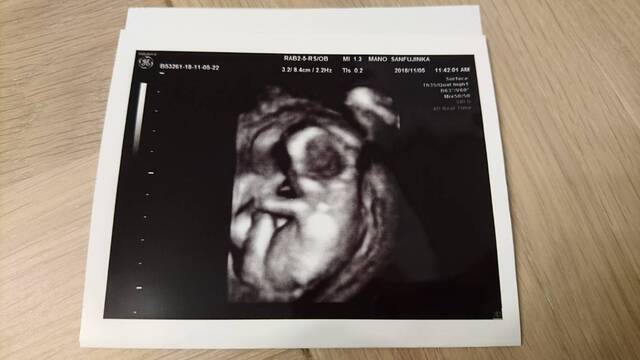

15週1日(15w1d・女の子)|トスカチーナ さん(24歳)

エコー写真撮影時のエピソード:

この頃はつわりが酷くて、毎日ゼリー生活をしてました。とっても辛かったのを今でも覚えています。でも栄養を取らなくては

と、食べれる時にタンパク質とかビタミン摂取をして、サプリも飲んでたりしました。健診の待ち時間ですら、椅子に座ってるだけでも辛かったなぁ。そんな中一ヶ月ぶりの健診でエコーをみて先生が赤ちゃんがこっちを見ているよ!写真好きなのかな?と言って見せてくれたエコー写真がこれでした。ちゃんと顔が見れるのは初めての事だったのでこっち見てるなんて嬉しい!と思っていましたが、エコー写真を見た第一声はえ、怖っっ!でした笑。宇宙から来たのか?!うちの子は宇宙人なのか?!とびっくりしました笑主人も、怖い!え、怖い!と、この写真を見て顔をしかめていましたが、今となっては笑い話になるエコー写真です。でもその時はほんと怖かった!!笑怖いとか言ってごめんねベビちゃん!